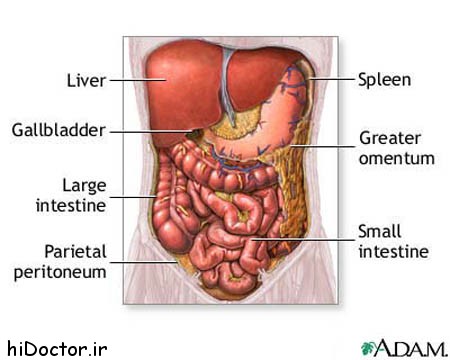

عکس داخل شکم انسان. در این همان طور که مشخص است شکم حالت بیضی شکل پیداکرده و این بیضی که کناره های شکم کشیده شده است. تعداد سلول های بدن انسان حدود ۳۷ ۲ تریلیون تخمین زده شده اند. Abdomen که در زبان عامه به غلط به آن دل نیز می گویند در آناتومی به قسمتی از تنه گفته می شود که مابین دیافراگم از بالا و سطح فوقانی لگن خاصره از پایین قرار دارد. ربات دیدنی ربات انساننمای چینی به صورت یک دختر جوان ساخته شده و جیا جیا نامگذاری شده است این ربات طوری برنامهریزی شده که میتواند صحبت کند و احساسات خود را از طریق تغییرات در چهره حالات.

شکل دوم شکم مادری را نشان می دهد که جنین دختر دارد. وحشت مادر از عکس سونوگرافی جنین داخل شکمش عکس. تصاویر جالب از داخل مغز و نخاع انسان آخرین نیوز. بدن انسان کل ساختار انسان است که سر گردن تنه سینه و شکم دو بازو و دست ها و دو ساق پا و پاها را شامل می شود.